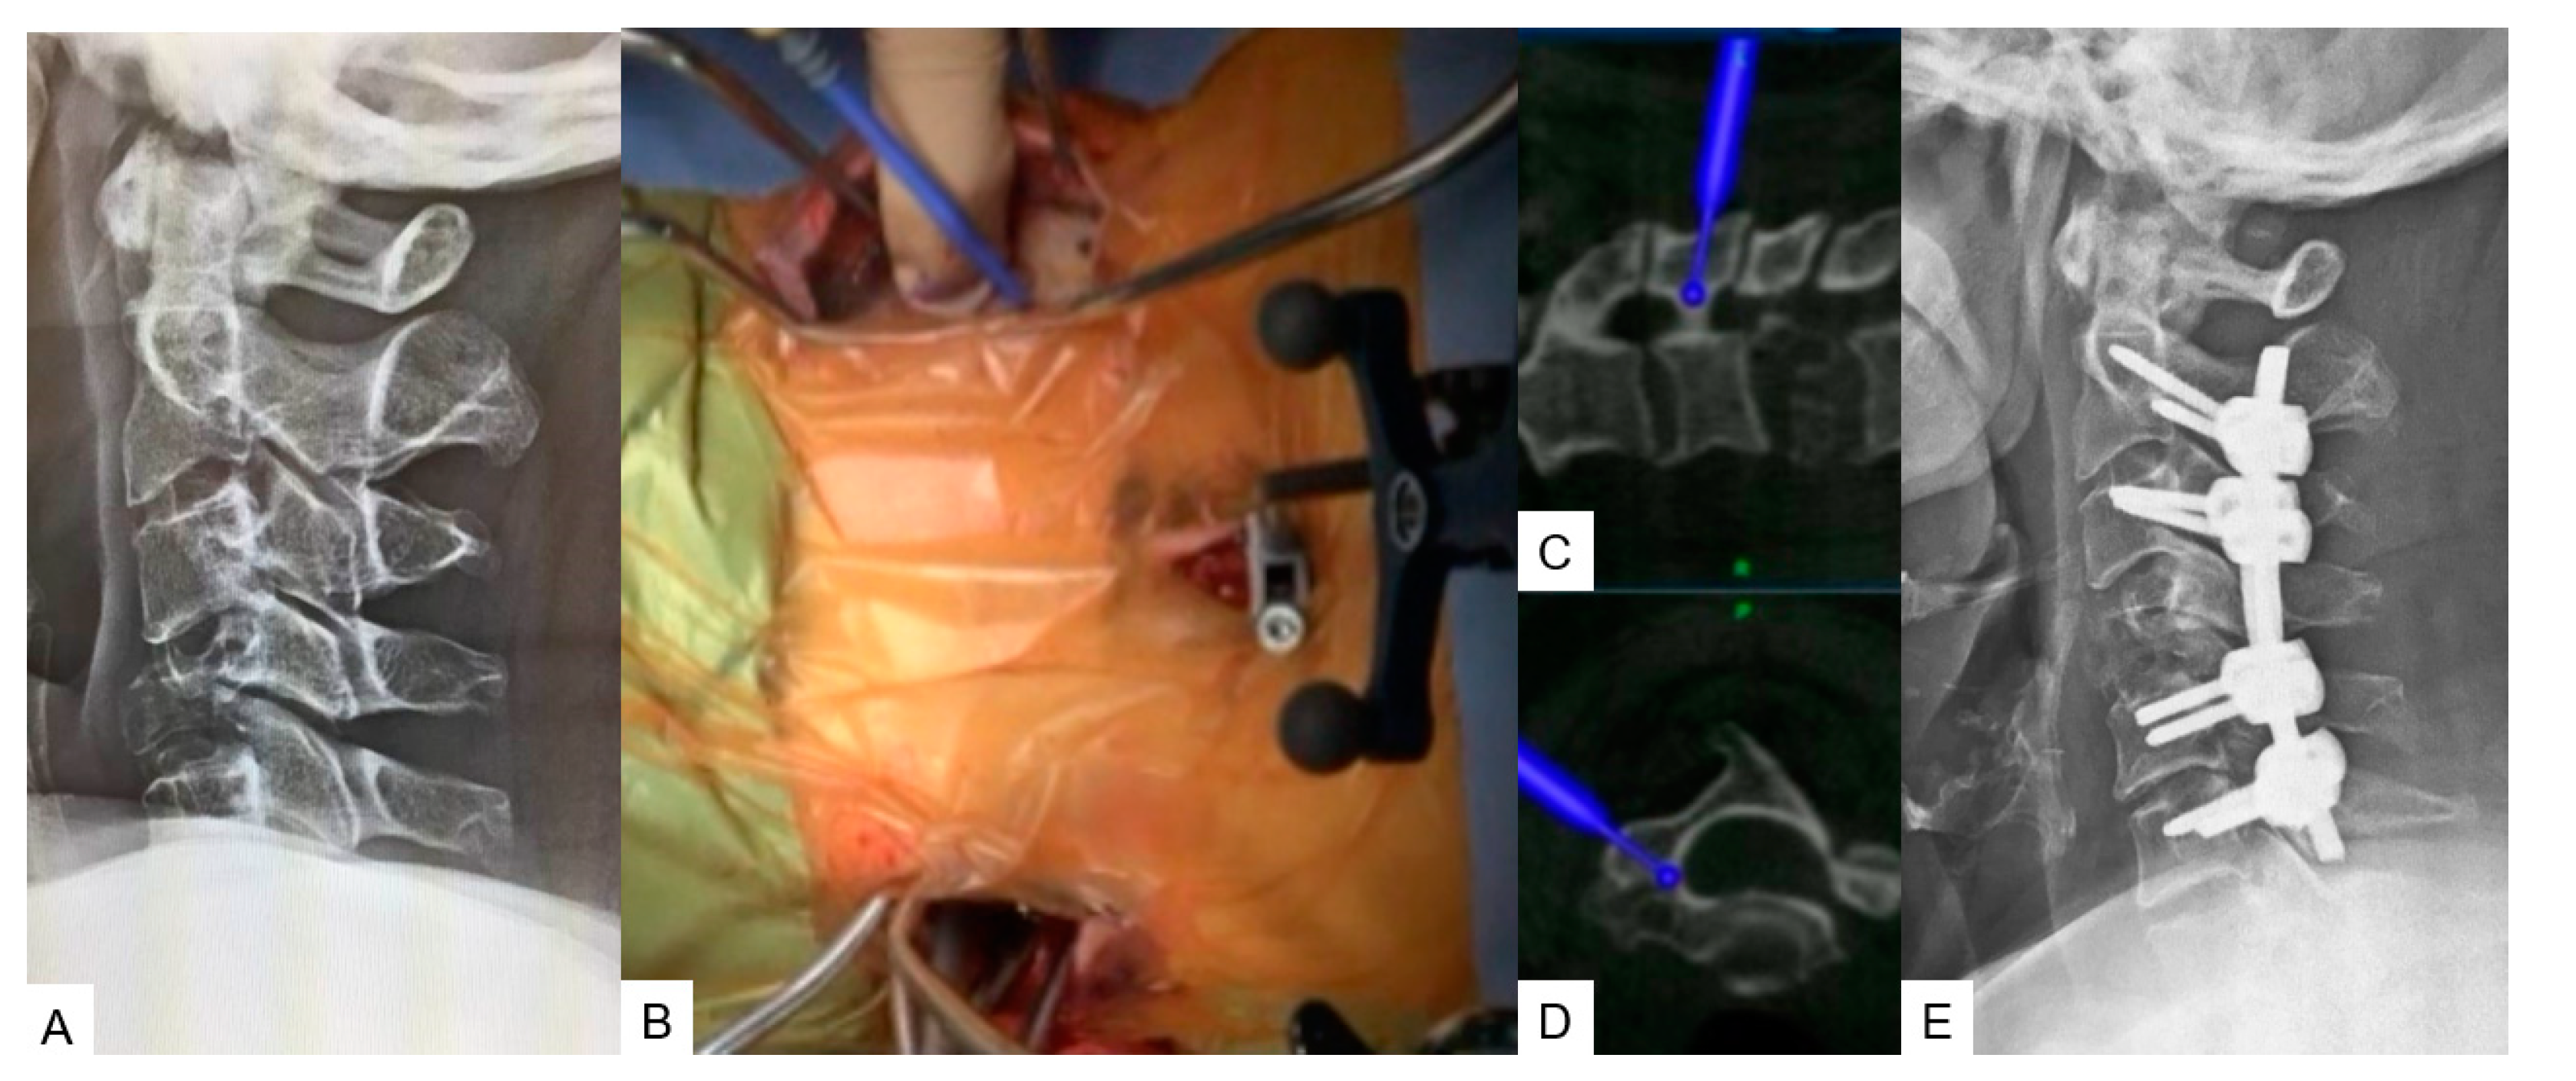

A: Preoperative cervical lateral radiogram, B: Intraoperative image, C: Intraoperative sagittal navigation image, D: Intraoperative axial navigation image, E: Postoperative cervical lateral radiogram.

Figure 5. Case 5, 62 years old female, Brest cancer, C4 metastasis, C2-6 posterior fusion.

2.2.4. Minimally Invasive Cervical Pedicle Screw Fixation (MICEPS)

During this technique, the patient’s positioning is very important. Thus, it is recommended that prone position with a carbon Mayfield cranial support on a Jackson frame which provides additional stability. Initially a small incision at the prominent C7 spinous process for reference frame attachment is advised, followed by an O-arm scan. Preoperatively CT scan verification for pedicle anatomy should be performed and studied. Ideally, bilateral 4cm skin incisions after navigation verification are enough for C3-C6 fixation. At the end, a new O-arm scan should be performed for verification of anatomical pedicle screw placement. During open posterior cervical screw fixation, complications such as high infection rates, postoperative pain or kyphotic deformity are frequent met. Thus, with this lateral minimal technique it is feasible to reduce this rate due to minimal surgical exposure.